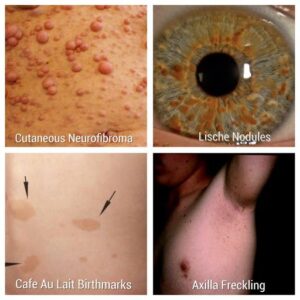

نوروفیبرومهای ناشی از نوروفیبروماتوز نوع ۱ ممکن است روی پوست و زیر آن، معمولاً در دوران کودکی، قابل مشاهده باشند. این تومورها عموماً بدون درد هستند و ممکن است مانند خالهای گوشتی نرم و لاستیکی احساس شوند. نوروفیبرومها ممکن است به صورت جداگانه، در خوشههای کوچک یا در سراسر بدن رشد کنند. همچنین NF1 با لکههای مادرزادی رنگدانهای معروف به لکههای پوستی شیر قهوه یا کافه او لاته همراه است. علاوهبراین، کودکان، نوجوانان و بزرگسالان ممکن است در نواحی زیر بغل و کشاله ران خود دچار کک و مک شوند.

- کک و مک در زیر بغل یا کشاله ران

- تومورهای بزرگ و نرم به نام نوروفیبرومهای پلکسیفرم که ممکن است رنگ تیره داشته باشند و در زیر سطح پوست پخش شوند

- تومورهای کوچک و لاستیکی پوست به نام نوروفیبرومهای گرهای

اگر دو مورد از ویژگیهای زیر در فرد ظاهر شود، باید مشکوک به NF1 تشخیص داده شود:

- شش یا بیشتر لکهی تیره با قطر ۱.۵ سانتیمتر یا بیشتر در افراد بالغ، یا با قطر ۰.۵ سانتیمتر یا بیشتر در افراد نابالغ

- داشتن دو یا چند نوروفیبروما از هر نوع، یا یک یا چند نوروفیبرومای پلکسیفرم (عصبی که به دلیل رشد غیرطبیعی سلولها و بافتهایی که عصب را میپوشانند ضخیم و بدشکل میشود)

- وجود کک و مک در زیر بغل یا کشالهی ران

- وجود دو یا چند گره لیش (نوعی اختلال در عنبیه چشم)